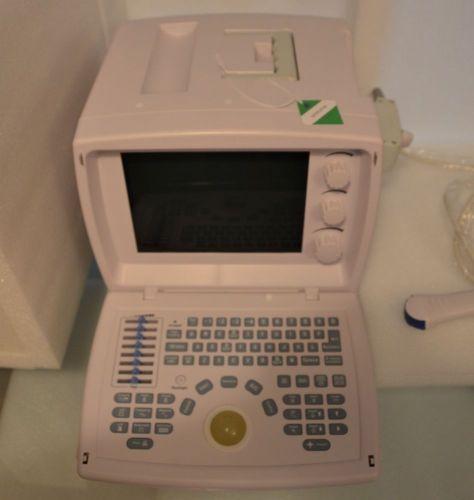

Aloka SSD-500 Portable Ultrasound - can be used for Veterinary with Warranty

Aloka SSD-500 Portable Ultrasound System for Veterinary or Human with Warranty!

Veterinary Portable Ultrasound with Transducer - USA - Free carrying bag